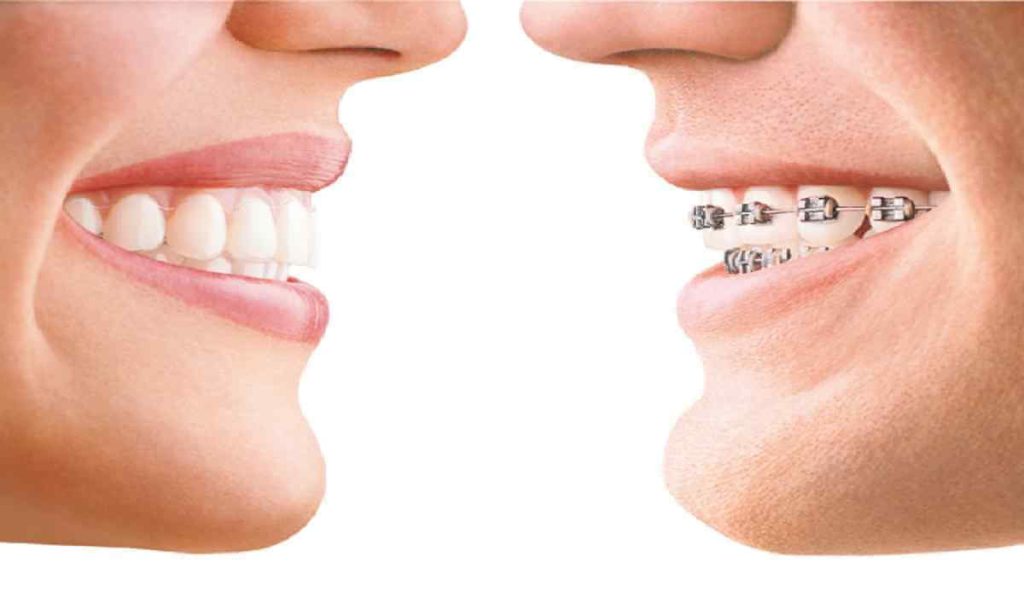

انتخاب روش درمانی: بسته به میزان ناهنجاری، روشهایی مانند براکتهای فلزی، سرامیکی، الاینرهای شفاف یا ارتودنسی متحرک انتخاب میشوند.

فواید و محدودیتهای درمان ارتودنسی نقش مهمی در تصمیمگیری برای اصلاح ناهنجاریهای دندانی دارد. این روش میتواند مشکلاتی مانند نامرتبی دندانها، ناهماهنگی فک و اختلالات جویدن را برطرف کرده و سلامت دهان و دندان را بهبود ببخشد. از طرفی، ارتودنسی با افزایش نظم دندانها، رعایت بهداشت دهان را آسانتر کرده و از پوسیدگی و بیماریهای لثه جلوگیری میکند. بااینحال، این درمان محدودیتهایی نیز دارد؛ از جمله طولانی بودن دوره درمان، هزینههای بالا و نیاز به مراقبت مداوم. برخی بیماران نیز ممکن است در روزهای ابتدایی استفاده از دستگاههای ارتودنسی، ناراحتی و حساسیت تجربه کنند. در این مقاله، به بررسی دقیق فواید و چالشهای ارتودنسی خواهیم پرداخت.

ارتودنسی یکی از روشهای رایج دندانپزشکی برای اصلاح ناهنجاریهای دندانی و فکی است. این درمان به بهبود جایگاه دندانها، تنظیم بایت و افزایش سلامت دهان کمک میکند. فواید و محدودیتهای درمان ارتودنسی بسته به شرایط بیمار، نوع روش مورد استفاده و رعایت مراقبتهای لازم متفاوت است. هدف اصلی ارتودنسی، ایجاد تراز مناسب بین دندانها و فکها است تا عملکرد دهان بهبود یابد و از مشکلاتی مانند پوسیدگی و بیماریهای لثه جلوگیری شود.